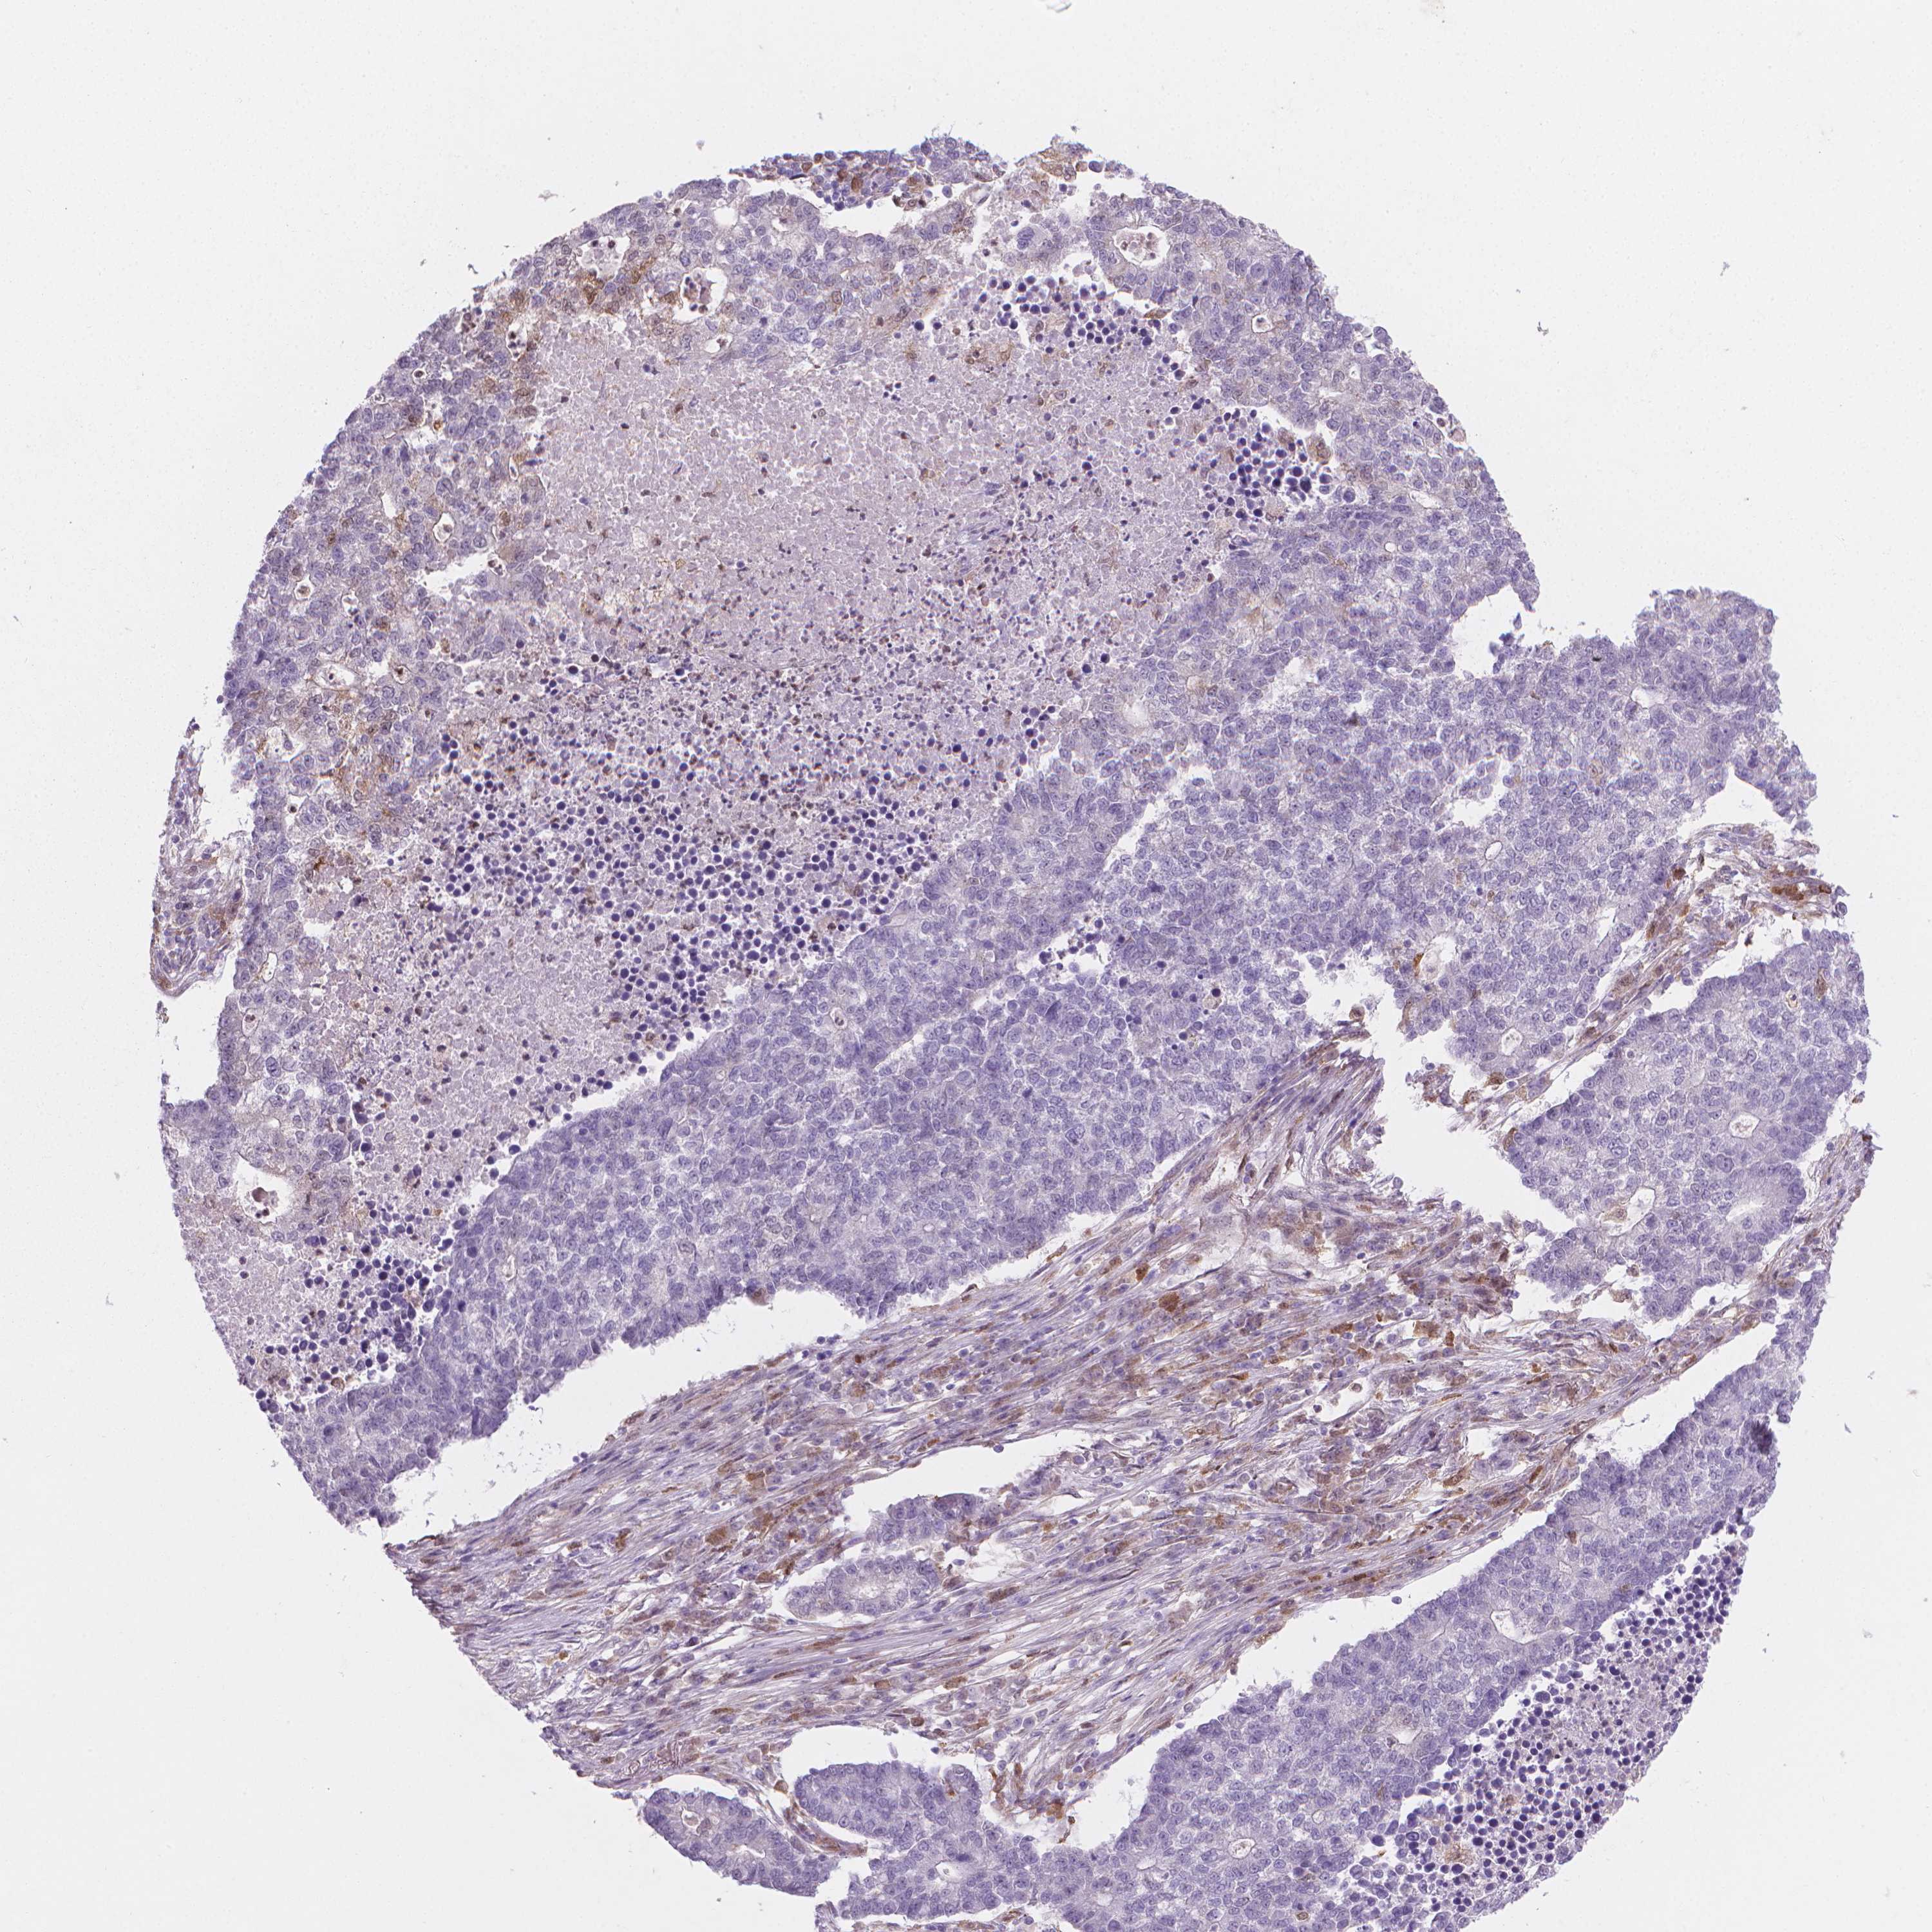

LUNG ADENOCARCINOMA (VALIDATION) - Interactive survival scatter ploti

The Survival Scatter plot shows the clinical status (i.e. dead or alive) for all individuals in the patient cohort, based on the same data that underlies the corresponding Kaplan-Meier plots. Patients that are alive at last time for follow-up are shown in blue and patients who have died during the study are shown in red.

The x-axis shows the expression levels (FPKM) of the investigated gene in the tumor tissue at the time of diagnosis. The y-axis shows the follow-up time after diagnosis (years). Both axes are complimented with kernel density curves demonstrating the data density over the axes. The top density plot shows the expression levels (FPKM) distribution among dead (red) and alive patients (blue). The right density plot shows the data density of the survived years of dead patients with high and low expression levels respectively, stratified using the cutoff indicated by the vertical dashed line through the Survival Scatter plot. This cutoff is automatically defined based on the FPKM cutoff that minimizes the p-score. The cutoff can be changed by dragging the vertical line or by entering a cutoff value in the square labeled "Current cut-off".

Under the Survival Scatter plot the p-score landscape (black curve; left axis) is shown together with dead median separation (red curve; right axis). Dead median separation is the difference in median mRNA expression between patients who have died with high and low expression, respectively. It is calculated as follows: median FPKM expression of dead patients with high expression - median FPKM expression of dead patients with low expression. This is intended to aid the user in visually exploring custom cutoffs and the associated p-scores and dead median separation.

Individual patient data is displayed and can be filtered by clicking on one or more of the category buttons on the top of the page. Categories describing expression level and patient information include: high, low, alive, dead, female, male and tumor stages. The scale of the x-axis can be toggled between linear and log-scale by clicking on the "x log" button. Mouse-over function shows TCGA ID, patient information and mRNA expression (FPKM) for each patient.

& Survival analysisi

Kaplan-Meier plots summarize results from analysis of correlation between mRNA expression level and patient survival. Patients were divided based on level of expression into one of the two groups "low" (under cut off) or "high" (over cut off). X-axis shows time for survival (years) and y-axis shows the probability of survival, where 1.0 corresponds to 100 percent.

TNFAIP2 is not prognostic in Lung Adenocarcinoma (validation)

Best expression cut offi

Based on the FPKM value of each gene, patients were classified into two groups and association between prognosis (survival) and gene expression (FPKM) was examined. The best expression cut-off refers the FPKM value that yields maximal difference with regard to survival between the two groups at the lowest log-rank P-value. Best expression cut-off was selected based on survival analysis .

When clicking on this number, the vertical dashed line indicating cut-off, the interactive survival plot, and the Kaplan-Meier curve will be adjusted to show results based on the best expression cut-off.

: 44.2

P scorei

Log-rank P value for Kaplan-Meier plot showing results from analysis of correlation between mRNA expression level and patient survival.

N/A

TCGA RNA samplesi

RNA-seq data is reported as average FPKM (number Fragments Per Kilobase of exon per Million reads), generated by the The Cancer Genome Atlas (TCGA) .

Normal distribution across the dataset is visualized with box plots, shown as median and 25th and 75th percentiles. Points are displayed as outliers if they are above or below 1.5 times the interquartile range. FPKM values of the individual samples are presented next to the box plot.

Average pTPM 75.9

Number of samples 105